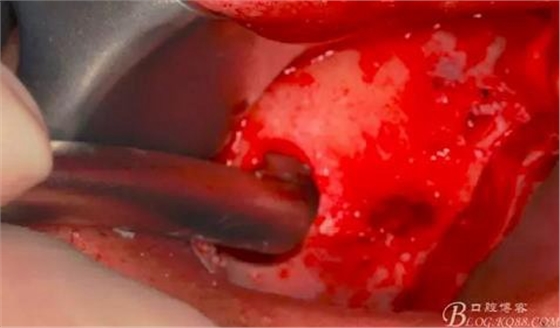

使用窗口擴(kuò)大鉆,這也是這套工具盒里一個(gè)亮點(diǎn),其前端是圓形高度光滑的,鉆體是有側(cè)切功能的。工作時(shí)用光滑的圓頭頂開已經(jīng)剝離的竇膜,用鉆體部分將窗口周邊不規(guī)則的部分磨掉,同時(shí)可以擴(kuò)大窗口。